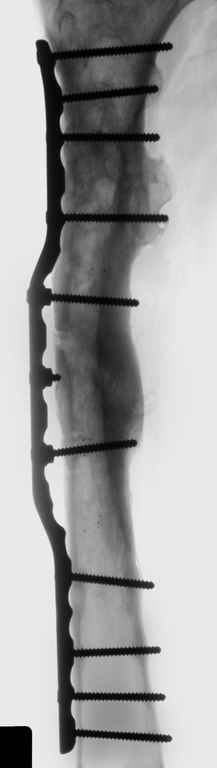

В ноябре этого года я обращался с просьбой о помощи в выборе тактики лечения больной с деформацией бедра на почве фиброзной дисплазии. Были получены интересные и очень полезные советы по операции.

Хотелось бы показать, что получилось в результате.

Операция выполнялась с помощью А.Н.Челнокова. Очень понравилась технология выполнения блокируемого остеосинтеза с использованием спицевого дистрактора, модифицированный гвоздь с латерализованным проксимальным отделом и возможностью многовинтовой фиксации проксимального и дистального участков бедра.